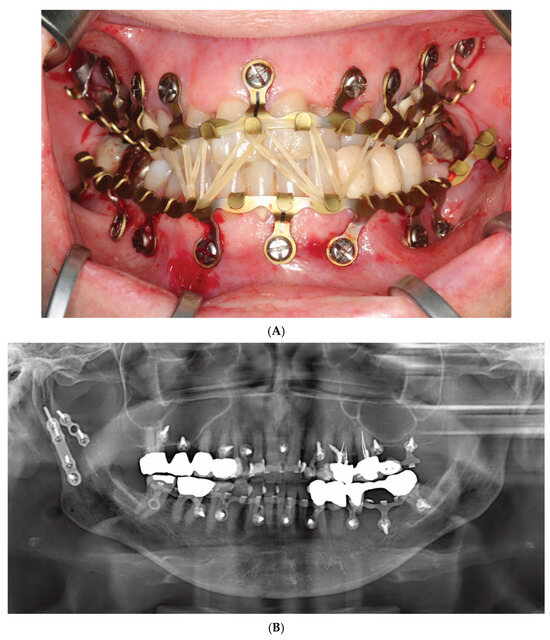

Figure 4.

(A) Clinical case example—intraoperative view of Zimmer Biomet OmniMax MMF devices divided into 4 segments for treatment of a triple mandibular fracture—bilateral condylar base and symphyseal midline. A dental splint (Titanium Trauma Splint, Medartis, Basel, Switzerland) resin bonded (acid etching technique) to the outer surfaces of the teeth of the anterior maxillary arch supports the repositioned medial upper incisors. The two maxillary segments represent the shortest possible plate variant consisting of a single mounting tab containing two slot apertures, with 2.0 four-hole miniplate visible in open anterior vestibulum approach. Of note: the standoff mechanism has been implemented for all screws—annular screw grooves fully seated in the slots. (B) Previous case cont’d. Postoperative panoramic X-ray after placement of OmniMax arch bars, ORIF—via transoral vestibular and preauricular transparotid approaches. Miniplate fixation of the condylar base fractures. Four-hole superior border (tension band) miniplate fixation in combination with a six-hole 2.4 inferior border plate. The arch bar retaining screws appear inserted correctly in the interradicular spaces. Source/origin: Photograph collection—C.P. Cornelius.

During continuous insertion of an OmniMax self-drilling screw, the second thread portion will engage the rim of the slot aperture. Owing to the different lead of the threads, with further advancement into the bone, the plate will be raised towards the head of the screw until the rim of the slot will be finally seated into the annular retention groove of the screw and held there by tight friction. For the plate, once seated within the screw’s locking groove, the standoff height can be tuned by turning the screw out of or into the bone. The gap can be further established and adjusted without a spacer tool.

Within the aperture of a slot, the screw position can be slid horizontally across a range of about 5–6 mm. Depending on its length, a minimal number of four screws per bar (Figure 3 and Figure 4A,B) or of two for a single section bar-segment (Figure 5A,B) is required to provide rotation stability.

To date, there is only one completed clinical study comparing the OmniMax MMF System with conventional Erich arch bars (EABs) (Aukerman et al. 2022) [36]. More precisely, this retrospective chart review compares 23 patients treated with the OmniMax hybrid with 18 patients having received EABs. The demographic data of both groups were homogenous. The assessment parameters were the mean total duration of surgery (surprisingly not the time for installation of the MMF devices!) and short-term complications including unexpected return to OR, 30-day postoperative infection rate, neuropathy, malocclusion and facial contour deformities. The indications for surgery were not reported. The mean total operating time was 84.9 min with OmniMax compared to 96.6 min with conventional EABs; this difference was not statistically significant. None of the short-term complications differed between the patient groups. The largest difference was exhibited for malocclusion—occurring in 9% (2/22) patients after the OmniMax MMF treatment versus 22% (4/18) patients with EAB.

A US clinical trial registration of a single-cohort study for clinical evaluation of the OmniMax MMF System (ClinicalTrials.gov ID: NCT03075865) dates to 2017. It was conceived as a multicenter prospective observational clinical trial. The investigative aim was to evaluate the efficiency of the OmniMax Hybrid MMF System in ORIF of mandibular fractures. Patient enrollment began in June 2017. A brief interim report presented outcomes for 19 patients (Morio et al. 2018) [37]. The mean application time for the OmniMax MMF hybrids was 12.8 ± 3.0 min. The average postoperative wearing period of hybrid MMF assemblies was 51.1 ± 9.7 days. Healing was uneventful in all cases.

Regular oral hygiene screening during the MMF interval showed that 78.9% (n = 15/19) had maintained or improved hygiene.

The time for removal of the devices was to 2.7 ± 1.2 min.

No glove perforations or accidental skin punctures during device application or removal were documented.

Postoperative CBCT analyses showed no screw contact in 91% of 300 tooth roots, whereas 8.3% had minor root contact and 0.7% had major root contact but without need for further treatment.

The authors concluded that interradicular screw insertion can be accomplished with minimal risk using appropriate preoperative imaging.

At the final visit, 15.8% (n = 3/19) of cases had injured periodontal structures, 1 case (5.2%) demonstrated mucosal screw (device) overgrowth and there was no gingival necrosis.

In terms of Quality of Life (QoL) metrics, the patients had minimal complaints at the end of treatment: the mean comparative pain score (0–10 scale) decreased from 5.21 preoperatively to 1.89 postoperatively prior to device removal.

Meanwhile, the recruiting phase (39 patients enrolled) for the trial was completed. The last study update was submitted to ClinicalTrials.Gov in July 2021 and the final results have not yet been posted (current status: February 2025) or published.